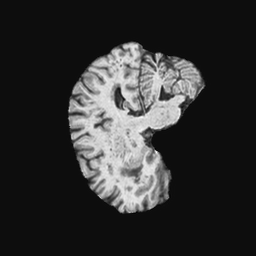

Exp. 2: Fetal brain data is used to test the robustness of our approach under real conditions. Fetuses younger than 30 weeks very often move a lot during examination. Fast MRI sequences allow artifact free acquisition of individual slices but motion between slices corrupts consistent 3D information. Fig. 3 shows that our method is able to accurately predict also under these conditions. For this experiment we use from three orthogonally overlapping stacks of ssFSE slices covering the fetal brain with approximately 20-30 slices each. We are ignoring the stack transformations relative to the scanner and treat each individually. For , 28 clinically approved motion compensated brain reconstructions are resampled into a volume with spacing. A density of 500 unique sampling normals has been chosen via the Fibonacci sphere sampling method with 25 sampling planes evenly spaced between -25 to +25 on the Z-axis. This gives a plane spacing of 2mm, sampling only the middle portion of the fetal brain. Training took approximately 10hrs for 30 epochs. Prediction, i.e., the forward pass through the network, takes approx. 12 ms/slice.

Here we show for Exp. 1, Exp. 2, and Exp. 3 randomly selected examples of images that have been presented to the network (ground truth) compared to an image sampled at the predicted location.

In these experiments, we present a ground truth (GT) image to the network to estimate the respective transformation parameters needed to reorient the slice in its correct world co-ordinates. Using the transformation parameters, we generated a slice from the 3D atlas in the location where the network has predicted that slice should be (denoted as SVRNet).

The slices are compared side-by-side to give a visual representation of “where the slice really is” and “where the network thinks the slice is”.

0..5.2 Exp. 2:

Slices, from a motion corrupted MRI stack, are segmented and cropped. Since there is no ground truth for the queried images, an arbitrary fetal atlas is used for visualization in Fig. 11 and 12.